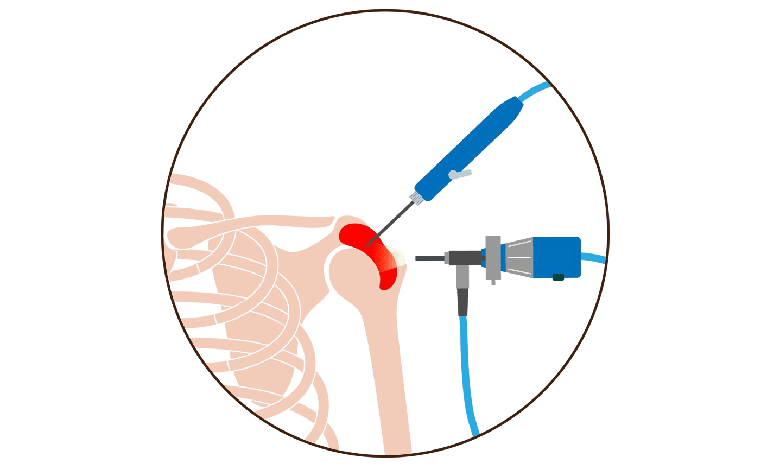

Sobre Dr. Luis Miguel Minero Rabatte

Con una amplia trayectoria en Ortopedia y Traumatología, el Dr. Luis Miguel Minero Rabatte se ha destacado por brindar tratamientos personalizados y de alta calidad en la Ciudad de México. Su compromiso con la salud y bienestar de sus pacientes lo ha posicionado como un referente en el área.